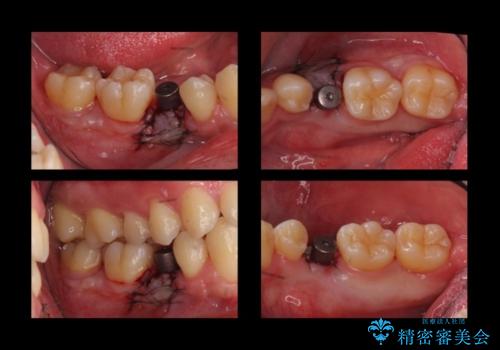

そのため、5番目のインプラントと、7番目の骨整形を同時に行い、整形で取れた7番目の骨をインプラント周囲に移植し、骨を増やすことにしました。

元々乳歯が残っていた場所であり、骨はたくさんあったため、インプラントを入れるのにそこまで支障はありませんでした。

ただし、奥歯の骨外科治療を同時に行うことで、同時についでに自分の骨を移植できるタイミングだったため行っておきました。